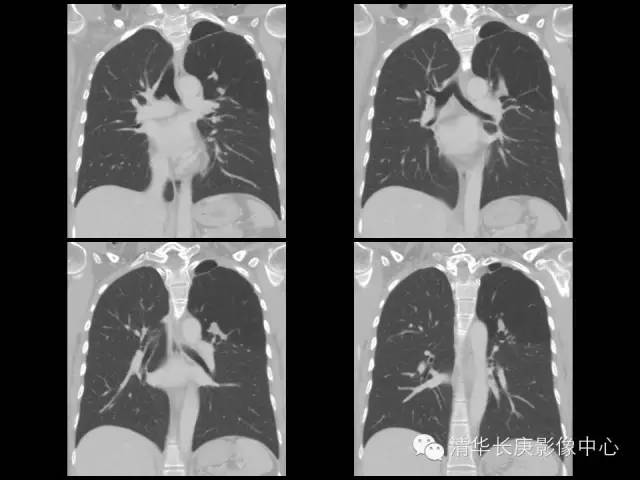

【病例】先天性支气管闭锁1例CT影像表现